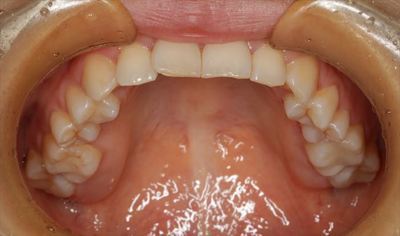

下顎です。

歯冠が崩壊した鋭縁で傷ついていた舌が落ち着いています。

慢性的な刺激は舌癌の要因のひとつと考えられていますので注意が必要です。